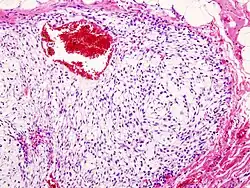

Histopathologic image of chondrosarcoma of the chest wall. Surgical resection of recurrent mass. H & E stain. | |